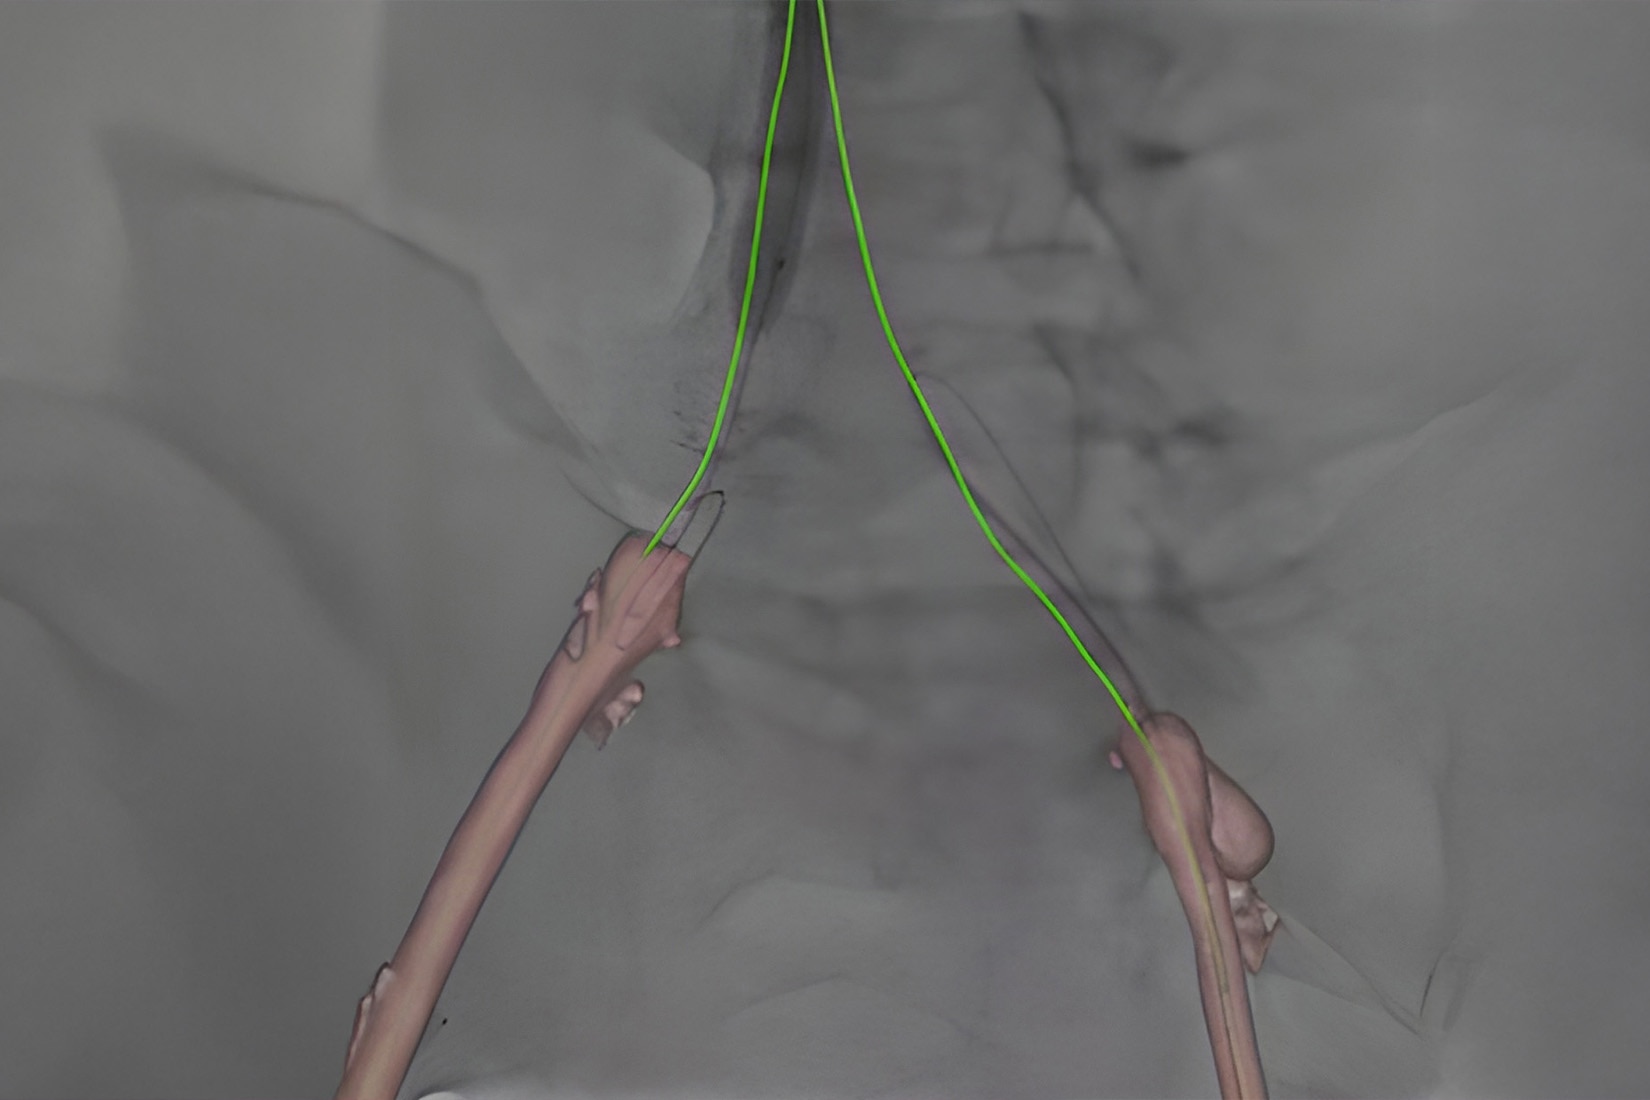

Vessel assist for peripheral

Vessel ASSIST delivers accurate and easy anatomy segmentation and accurate vessel quantification from 3D volumes. It also offers advanced 3D roadmap and augmented image guidance capabilities to guide catheter with confidence.

Plan

Automatically extract the bone and vessel anatomies. Edit vessel centerlines and bridge them through occlusions.

Guide

Select from the sub-volumes of vessels, centerlines, calcifications and landmarks to overlay on live fluoroscopy for 3D fusion guidance, with digital zoom, to guide recanalization.